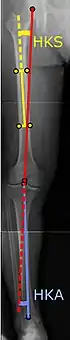

![]() |

Angles commonly measured before knee replacement surgery: |

To indicate knee replacement in case of osteoarthritis, its radiographic classification and severity of symptoms both should be substantial. Such radiography should consist of weightbearing X-rays of both knees: AP, lateral, and 30 degrees of flexion. AP and lateral views may not show joint space narrowing, but the 30-degree flexion view is most sensitive for narrowing. Full-length projections also are used in order to adjust the prosthesis to provide a neutral angle for the distal lower extremity. Two angles used for this purpose are:

- Hip-knee-shaft angle (HKS),[9] an angle formed between a line through the longitudinal axis of the femoral shaft and its mechanical axis, which is a line from the center of the femoral head to the intercondylar notch of the distal femur.[11]

- Hip-knee-ankle angle (HKA),[10] which is an angle between the femoral mechanical axis and the center of the ankle joint.[11] It is normally between 1.0° and 1.5° of varus in adults.[12]